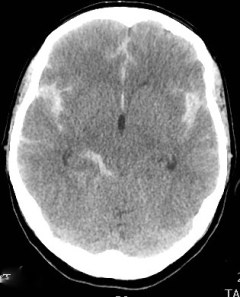

Grado 3- Coágulos localizado o/y capa vertical > 1mm de grosor.